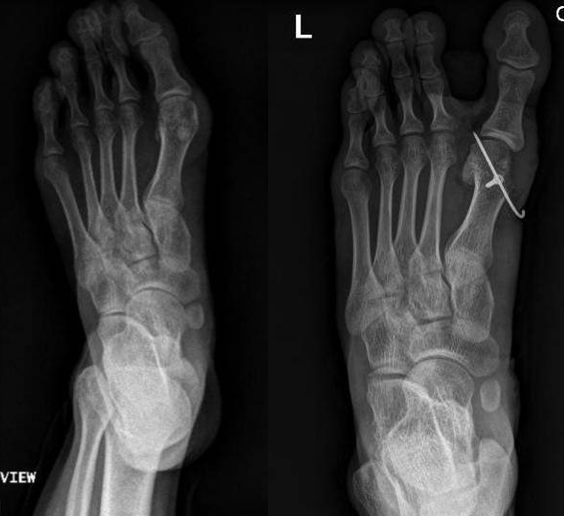

典型病例例1:姚X,女,78Y。

Chevron+第二跖骨Weil

例2:芦XX,男,21Y。

例3:朱XX,男,23Y。

例4:罗XX,女,60Y。

左足:第1-5跖趾关节脱位,足拇外翻。

胼胝体:第一跖骨内侧,第2/3跖骨头跖侧,第5跖骨头跖/外侧。

左足:第2-5趾爪形趾。

右足:第4趾爪形趾,趾间关节胼胝,疼痛。

右足:第5跖骨头跖/外侧胼胝。

CT重建:第1跖骨头破坏。

术式:左足:第1跖趾关节融合+第2-5跖趾关节成形术;右足:第4趾间关节融合+第5跖趾关节成形术